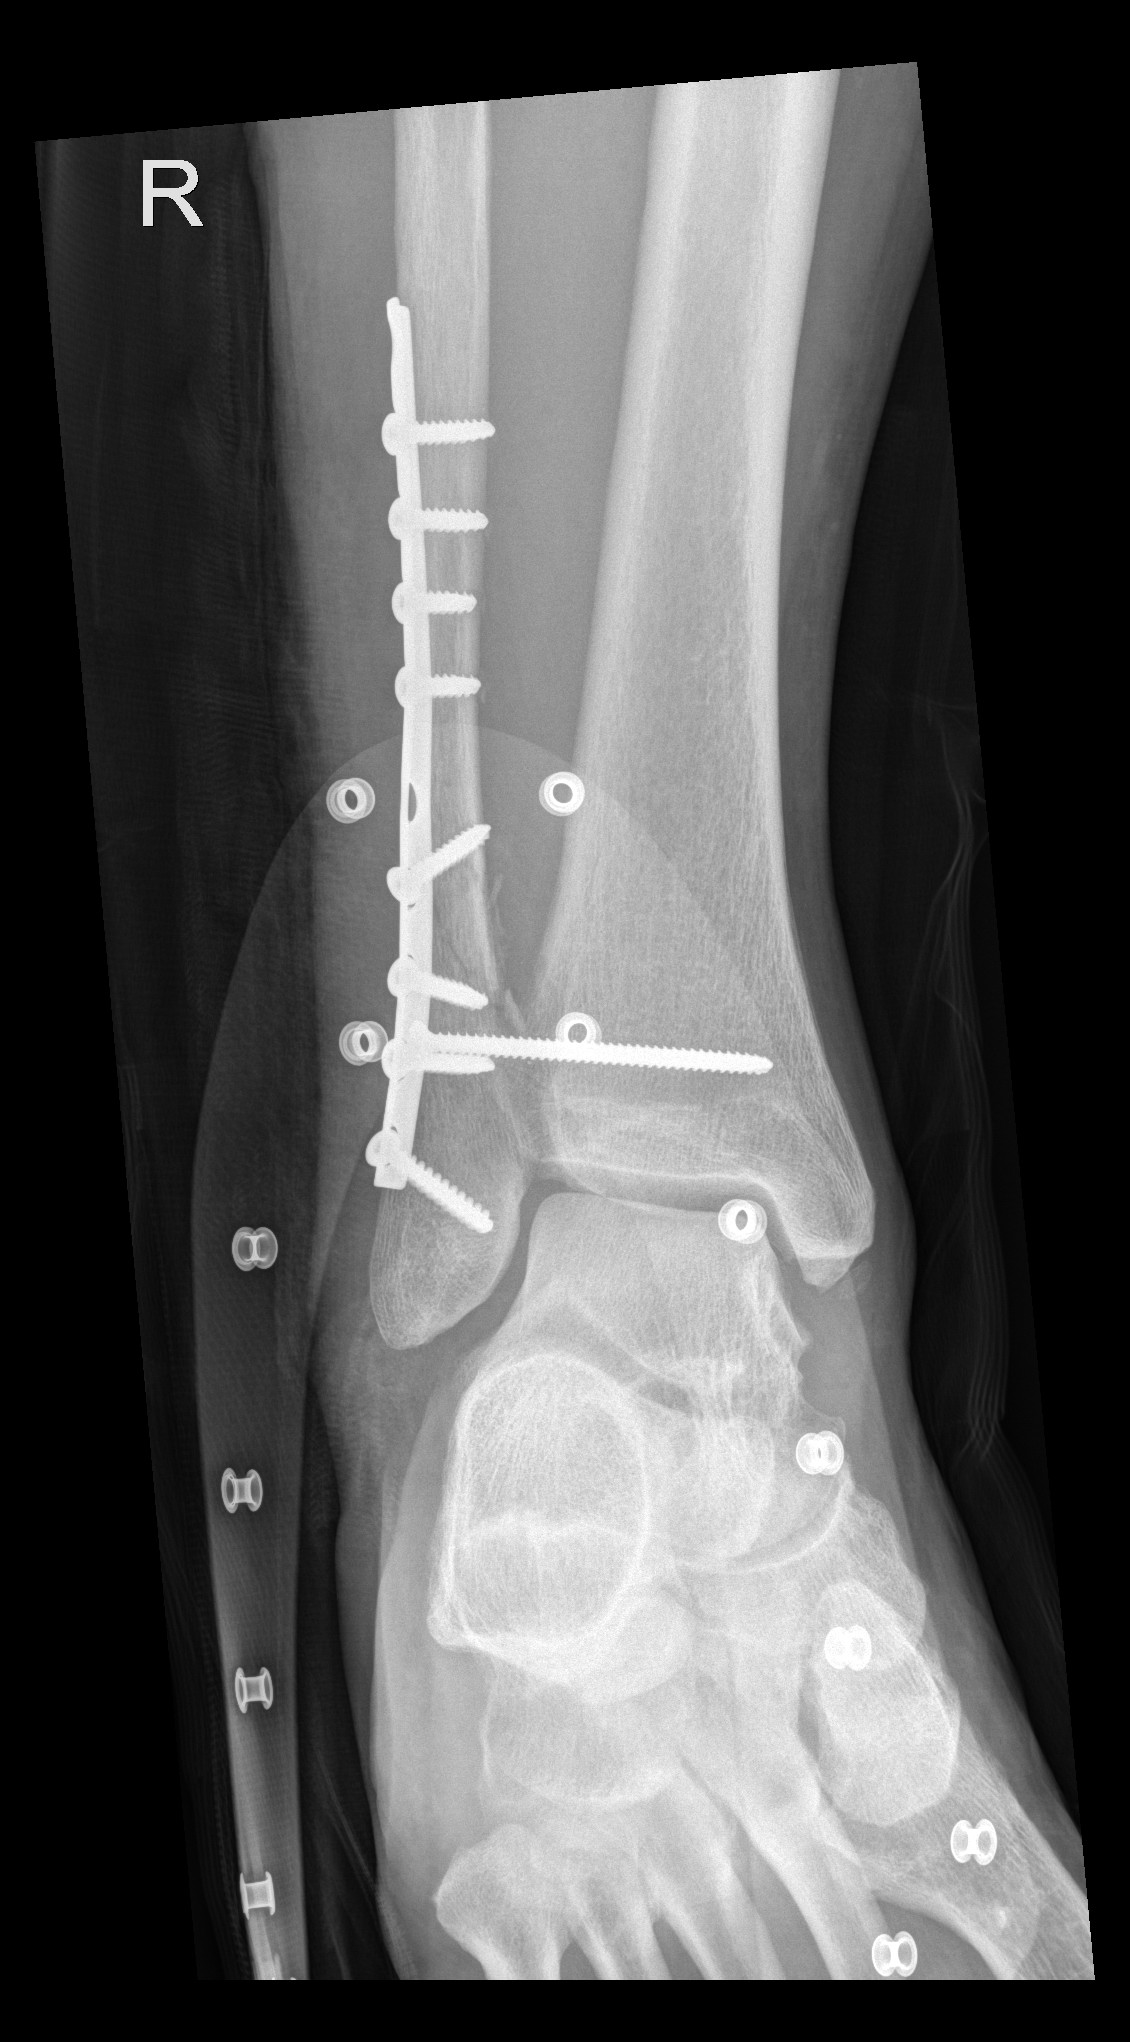

In der Notaufnahme konnte ich dann erstmals mein Bein frei machen. Die Besatzung der REGA verabschiedete sich und schon bald bestätigten die Röntenbilder einen Bruch des Wadenbeins. Ich war mindestens etwas erleichtert, dass es kein siebenfacher Trümmerbruch war wie letztes Mal, aber in dem Fall ist das eher Zufriedenheit auf tiefem Niveau.

Die lange Schraube stabilisiert Schien- und Wadenbein, bis der genähte Syndesmosebandriss ausgeheilt ist. Eine Syndesmose ist eine bandartige Verbindung zwischen zwei Knochen, die aus straffem Bindegewebe besteht und als «unechtes Gelenk» gilt; sie stabilisiert vor allem das obere Sprunggelenk zwischen Schien- (Tibia) und Wadenbein (Fibula) und ermöglicht eine begrenzte Bewegung, wobei eine Verletzung zu Instabilität führt und oft eine operative Stabilisierung erfordert. Diese Stabilisierungschraube muss in 6 Wochen wieder raus, danach ist das Gerüst wieder voll belastbar.

Die Schiene kann in frühestens 9 Monaten herausoperiert werden, ich werde den Termin dann aber eher im November vereinbaren.